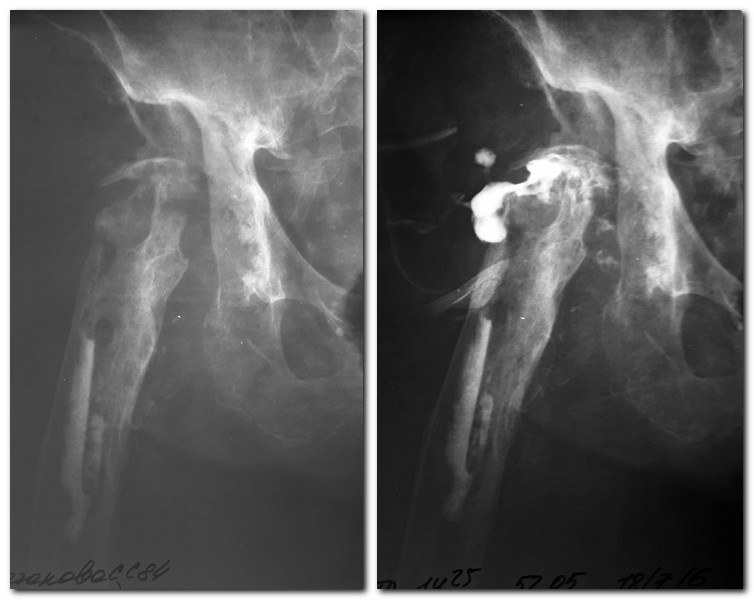

Больная,84 года,удаление протеза тазобедренного сустава в 2014

году,парапротезная инфекция.2 года свищей не было.Пациентка активна,

признаков деменции нет. До удаления протеза преподавала в ВУЗе. Ходила и

ходит(пришла сама) с опорой при помощи ходунков с коррекцией укорочения

ортопедической обувью. В канале остатки костного цемента. Удалить его

тогда не удалось. Со слов больной на прошлой неделе вскрылся свищ,

большое количество гнойного отделяемого выделилось.

В настоящее время такая картина (pRn-грамма,фистулография).Свищ со

скудным серозно-геморрагическим отделяемым. Посев сегодня взяли, в

работе. Повышены маркеры воспаления: СОЭ, Лей без сдвига.СРБ, фибриноген

в работе. Задумываюсь о ревизии, удалении цемента из канала, пока

останавливает отсутствие заключения терапевта. Как цемент достать из

канала? Инструмент Synthes ревизионный недоступен. Такой объем операции

будет достаточным? Можно ли вообще обойтись без операции?

Антибиотикотерапия нужна или достаточно санации? Спасибо.